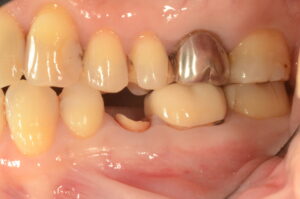

After

| 主訴 | 歯並びを治したい |

|---|---|

| 診断名 | 叢生(混雑した歯並び) |

| 年齢・性別 | 82歳、女性 |

| 治療期間・回数 | 4ヶ月間、来院回数4回 |

| 治療方法 | 歯と歯の間に0.5mmのやすりがけをして歯の横幅を修正し、マルチブラケット装置(ワイヤー矯正器具)にて歯を配列 |

| 費用 | 検査料 55,000円 基本矯正料 220,000円 処置料 5,500円 / 月 |

| デメリット・注意点 | 唇に装置が当たって口内炎になる可能性 歯根吸収の可能性 調整のたびに2〜3日程度、上下の歯が接すると痛みが生じる |